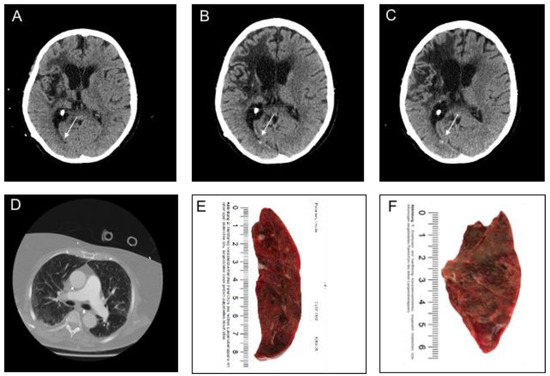

| Parenchymal Hemorrhage (n = 6) | |

| Location | |

| • Lobar, n (%) | 4 (66.7) |

| • Deep, n (%) | 1 (16.7) |

| • Infratentorial, n (%) | 1 (16.7) |

| Ventricular extension, n (%) | 1 (16.7) |

| SAH extension, n (%) | 1 (0) |

| Subarachnoid Hemorrhage (n = 11) | |

| Primary SAH, n (%) | 9 (81.8) |

| • Aneurysmal, n (%) | - |

| • Cortical, n (%) | 9 (81.8) |

| • Bilateral, n (%) | 4 (36.4) |

| • Ventricular extension, n (%) | - |

| Secondary SAH, n (%) | 2 (18.2) |

| Intraventricular Hemorrhage (n = 3) | |

| Isolated IVH | |

| • Supratentorial, n (%) | 3 (100) |

| • Infratentorial, n (%) | - |

| • SAH extension, n (%) | - |

| Secondary IVH *1, n (%) | 1 (33.3) |

| Subdural Hemorrhage (n = 1) | |

| Convexity, n (%) | 1 (100) |

| Bilateral, n (%) | - |

| SAH extension, n (%) | 1 (100) |